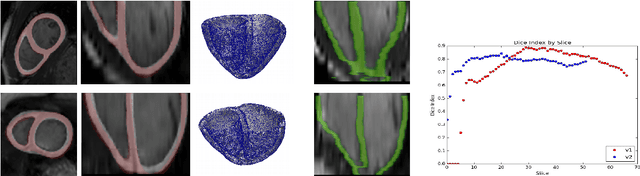

Abstract:We propose a method based on deep learning to perform cardiac segmentation on short axis MRI image stacks iteratively from the top slice (around the base) to the bottom slice (around the apex). At each iteration, a novel variant of U-net is applied to propagate the segmentation of a slice to the adjacent slice below it. In other words, the prediction of a segmentation of a slice is dependent upon the already existing segmentation of an adjacent slice. 3D-consistency is hence explicitly enforced. The method is trained on a large database of 3078 cases from UK Biobank. It is then tested on 756 different cases from UK Biobank and three other state-of-the-art cohorts (ACDC with 100 cases, Sunnybrook with 30 cases, RVSC with 16 cases). Results comparable or even better than the state-of-the-art in terms of distance measures are achieved. They also emphasize the assets of our method, namely enhanced spatial consistency (currently neither considered nor achieved by the state-of-the-art), and the generalization ability to unseen cases even from other databases.

Abstract:We present a novel automated method to segment the myocardium of both left and right ventricles in MRI volumes. The segmentation is consistent in 3D across the slices such that it can be directly used for mesh generation. Two specific neural networks with multi-scale coarse-to-fine prediction structure are proposed to cope with the small training dataset and trained using an original loss function. The former segments a slice in the middle of the volume. Then the latter iteratively propagates the slice segmentations towards the base and the apex, in a spatially consistent way. We perform 5-fold cross-validation on the 15 cases from STACOM to validate the method. For training, we use real cases and their synthetic variants generated by combining motion simulation and image synthesis. Accurate and consistent testing results are obtained.